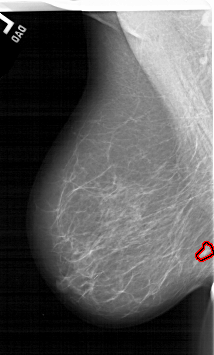

A_1464_1.RIGHT_MLO

RIGHT_MLO LINES 5761 PIXELS_PER_LINE 3826 BITS_PER_PIXEL 12 RESOLUTION 43.5 NON_OVERLAY

FILE: A_1464_1.LEFT_MLO.OVERLAY

TOTAL_ABNORMALITIES 1

ABNORMALITY 1

LESION_TYPE MASS SHAPE IRREGULAR MARGINS ILL_DEFINED

ASSESSMENT 4

SUBTLETY 2

PATHOLOGY MALIGNANT

TOTAL_OUTLINES 1

BOUNDARY